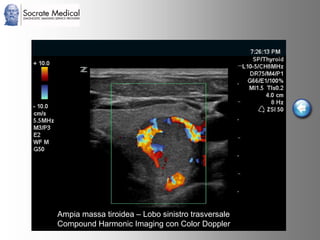

Il documento presenta la tecnologia della zone sonography, che promette una rivoluzione nel campo degli ultrasuoni, superando i limiti dei sistemi tradizionali grazie a metodi di acquisizione dati più veloci e una gestione delle informazioni migliorata. Questa tecnologia consente una maggiore definizione dell'immagine, una riduzione degli artefatti e un'ottimizzazione del processo diagnostico, con vantaggi in termini di tempo e costi. Inoltre, il channel domain processing e la zone speed technology offrono applicazioni avanzate e miglioramenti nella sicurezza diagnostica.